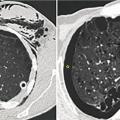

Parmi les patients d’une série française4 souffrant de pneumothorax spontané (n = 83), 85 % étaient fumeurs de tabac (n = 70) dont la moitié consommateurs de cannabis (n = 32), avec en moyenne un usage important de 30 JA (IC 25-75 : 10 à 31). Les scanners thoraciques ont montré un emphysème chez de nombreux sujets (50 % des consommateurs de tabac seul, 71 % des fumeurs tabac-cannabis). Dans ce dernier groupe, les malades étaient plus jeunes (35 ans vs 46 ans, p = 0,009) et consommaient moins de tabac en paquet-années (p = 0,02 ;figure ). Ainsi, fumer du cannabis, ajouté au tabac, majore le risque d’emphysème.

Parmi les patients d’une série française4 souffrant de pneumothorax spontané (n = 83), 85 % étaient fumeurs de tabac (n = 70) dont la moitié consommateurs de cannabis (n = 32), avec en moyenne un usage important de 30 JA (IC 25-75 : 10 à 31). Les scanners thoraciques ont montré un emphysème chez de nombreux sujets (50 % des consommateurs de tabac seul, 71 % des fumeurs tabac-cannabis). Dans ce dernier groupe, les malades étaient plus jeunes (35 ans vs 46 ans, p = 0,009) et consommaient moins de tabac en paquet-années (p = 0,02 ;